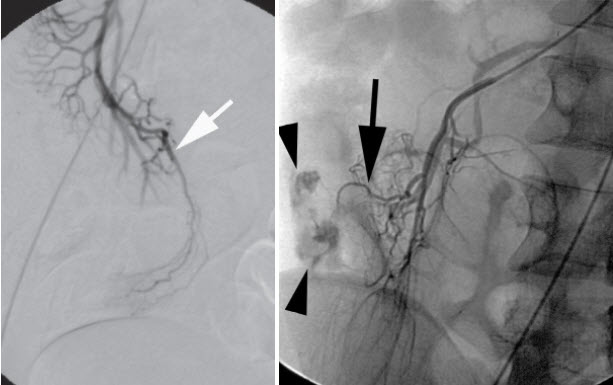

Chụp mạch số hóa xóa nền (DSA):.

Nó chỉ ra các nhánh động mạch mạc treo tràng trên bất thường hay sự thoát mạch của chất cản quang. Động mạch vitelline xuất phát như 1 nhánh hồi tràng của động mạch mạc treo tràng trên. (Hình 4). Phương pháp này có độ chính xác 59%. Hiện tại Bệnh viện của chúng tôi đã có phương tiện này.

Hình 4. Hình ảnh chụp DSA

* Nguồn: theo Levy A.D.(2004) [7]